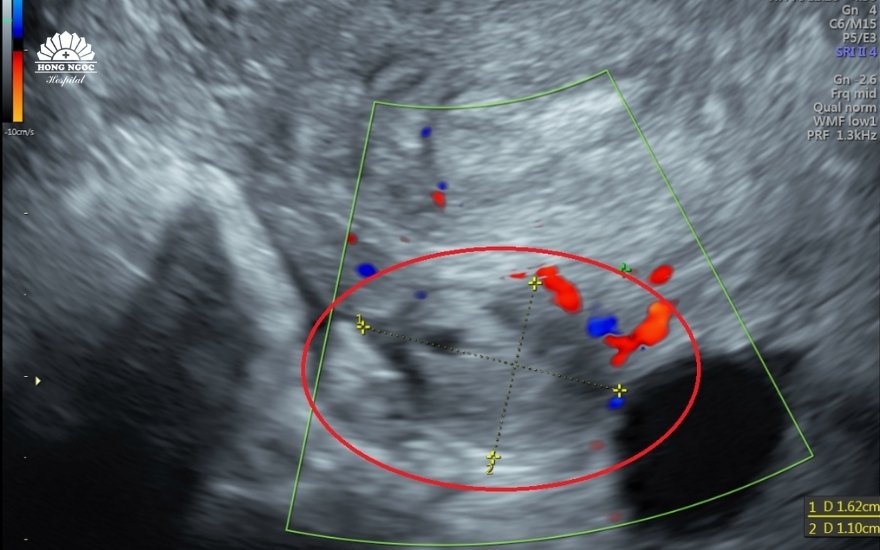

홍 응옥 종합병원 옌닌지점 산부인과 과장인 도 반 뚜(Do Van Tu) 제2 전문의는 "N.T.L 씨가 집에서 임신 테스트를 했을 때 두 줄이 나왔지만, 초음파 검사했을 때 자궁 내에서 배아를 확인할 수 없었습니다. 대신 좌측 난소에서 10x13mm 크기의 종괴가 발견되었고, 이를 자궁외 임신으로 의심했습니다. 따라서 환자의 생명을 보호하기 위해 수술이 필요할 수 있습니다."고 말했습니다.

초음파 영상에서는 좌측 난소에 11x15mm 크기의 종괴가 확인되었으며, 자궁외임신이 의심되었습니다.